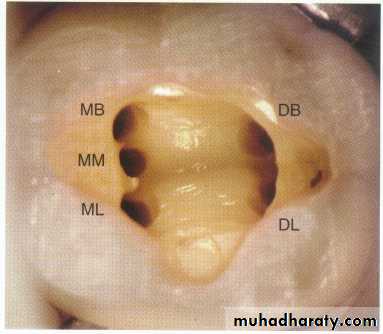

Maxillary first molar.

* Fourth canal (55-74% of teeth) located in the mesiobuccal root.Canal configuration is usually type II or type IV in mesiobuccal root

* The palatal and distobuccal roots usually present a type I configuration.* The length of this tooth is 22mm*Apical-buccal curvature of the palatal root.

* The palatal root slightly longer than the buccal roots.* The pulp chamber is quadrilateral in shape and wider buccopalatally than mesiodistally.* it has four pulp horns, the mesiobuccal is the longest and sharpest in outline.

* The distobuccal pulp horn is smaller than the mesiobuccal but larger than the two palatal pulp horns.* the floor of the pulp chamber is just apical to the cervix, rounded and convex towards the occlusal.

*the minor mesiobuccal canal if present lies on a line joining the main mesiobuccal and palatal canal orifices.*the distobuccal root is closer to the middle of the tooth than to the distal wall.

* The distobuccal canal is the shortest and finest of the three canals.* the palatal canal is the largest and longest of three canals and in 50% the canal curved buccally in apical third.